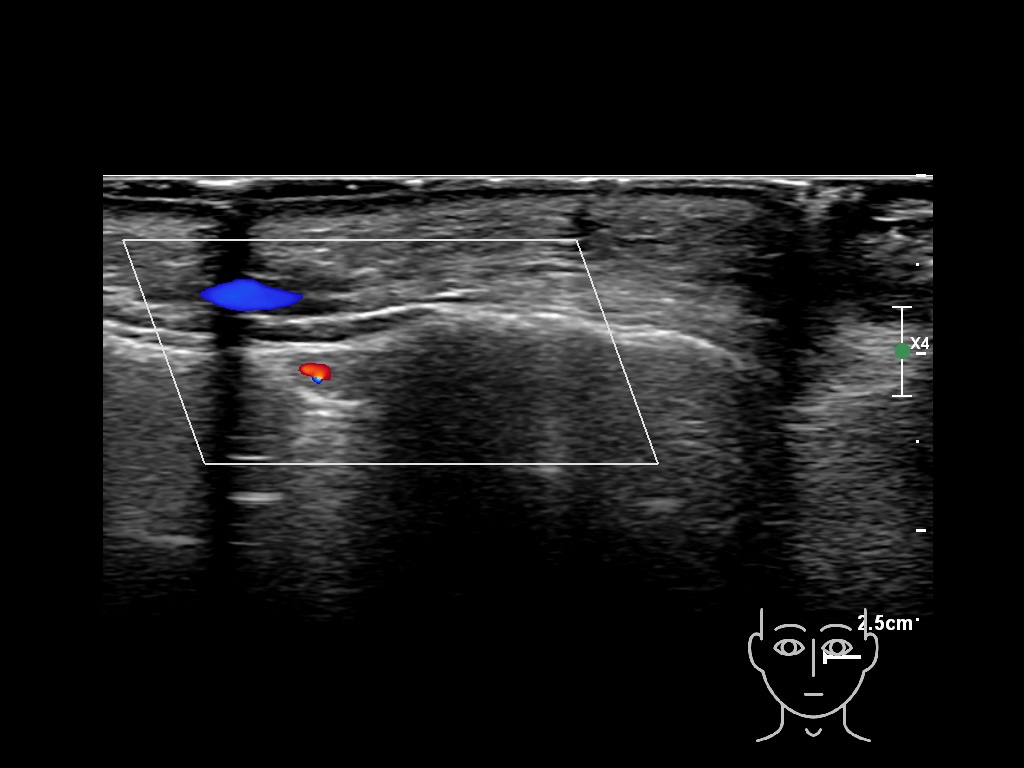

Study the first image to recognize the different layers. If you are sure about the layers, swipe to the second image to view the answer (if applicable).